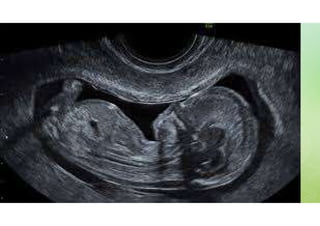

ultrassonografia

IMAGEM

O QUE É?

 A ultrassonografia é o exame de ultrassom que utiliza ondas

sonoras para gerar imagens do corpo humano.

 É um método muito utilizado para o acompanhamento pré-natal e

para avaliação de estruturas de partes moles do corpo

humano.

 Além disso, também pode ser utilizado para guiar procedimentos

intervencionistas, como biópsias e cirurgias.

 É um procedimento seguro, de baixo custo, não invasivo e que

não utiliza radiação ionizante.

 Portanto, é uma ótima ferramenta diagnóstica.

Eles são utilizados para visualizar os

órgãos internos do corpo, como:

Coração e vasos sanguíneos, incluindo a aorta abdominal e seus principais ramos;

Fígado;

Vesícula biliar;

Baço;

Pâncreas;

Rins;

Bexiga;

Útero, ovários e, em pacientes grávidas, o feto;

Olhos;

Glândulas tireóide e paratireóide;

Bolsa escrotal (testículos).